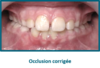

Le quad Helix est indiqué lorsque le palais est trop étroit : on parle d' articulé croisé  : les dents supérieures sont à l’intérieur des dents inférieures au lieu de les surplomber.

L'articulé croisé peut être unilatéral ou bilatéral.